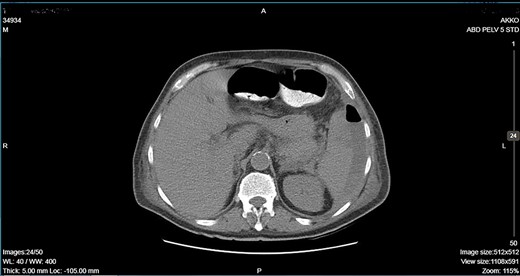

CT showing descending colon wall thickening in contact with the spleen and the tail of the pancreas and a subcapsular splenic abscess as well as splenic vein thrombosis.

A 64-year-old man presented to the emergency department with left pleuritic chest pain, anorexia and fever with rigors. His vital signs included a pulse of 130 beats/min, blood pressure of 108/51 mmHg, respiratory rate of 18 breaths/min, oxygen saturation of 95% and body temperature of 36.1°C. He had no relevant medical history. The patient was admitted to the hospital with the diagnosis of pneumonia based on his chest X-ray findings. The patient remained hemodynamically stable through the next day but developed a temperature of 39.2°C. A CT scan revealed a tumor of the splenic flexure that had invaded the spleen and pancreas via the transcoelomic route and created a subcapsular splenic abscess (Fig. 1). The CT scan also revealed splenic vein thrombosis located proximal to the tail of the pancreas. CT-guided percutaneous drainage of the abscess was scheduled for the following day. The patient’s clinical condition suddenly deteriorated and he became hemodynamically unstable. Abdominal distention with diffuse tenderness was identified via clinical examination, and laboratory tests revealed leukocytosis with a white blood cell count of 16.800/mm and anemia, with a hematocrit of 28.5%. An emergent CT scan revealed intraperitoneal rupture of the splenic abscess (Fig. 2). Intraoperative findings of an urgent surgical intervention included severe, diffuse purulent peritonitis with a large amount of pus mixed with blood clots in the peritoneal cavity that required cautious cleaning and thorough lavage. Furthermore, a large, hard, immovable tumor was identified in the splenic flexure of the colon. The tumor was tightly adherent to the spleen; we also noted the presence of intense inflammation and local fibrosis that extended to the surrounding tissues. En-block splenectomy and a wide left colectomy were performed followed by closure of the distant colon remnant using a linear stapler; furthermore, we also created an ostomy of the proximal colon remnant, similar to Hartmann’s procedure and drained the abdominal cavity. Transfusion of 600 ml of red blood cells was required. Extubation and postoperative recovery were uneventful, and the patient’s clinical status and parameters remained stable. Antibiotic treatment included meropenem 2 g thrice daily, metronidazole 500 mg thrice daily and amikasin 1 g once daily. The postoperative course was uneventful and the patient was discharged on postoperative day 12. Histopathological examination of the resected specimen revealed a 6 cm diameter perforated tumor adherent to an 18 × 13 × 6 cm spleen and a moderately differentiated grade 2 adenocarcinoma with infiltration to the pericolic fat. The resection margins were free of infiltration as were all of the 19 resected lymph nodes. A metastatic tumor, 2 cm in diameter, was identified in the spleen portal. The TNM stage was T3N0M1a (stage IVA disease), and the patient was referred to the Oncologic Department for adjuvant chemotherapy. He was administered eight cycles of Capecitabine that is changed into 5-fluorouracile + Oxaliplatin along with the necessary follow-up care. The patient has been disease-free for 2 years after the treatment.